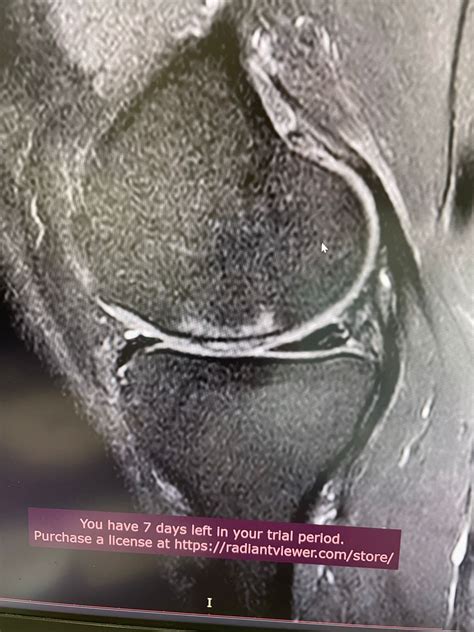

Surgeons Explain Exactly How To Fix Knee Cartilage Damage Using Cells